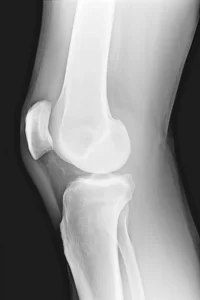

Glucosamine, Chondroitin, and MSM: Alleviating Knee Pain

Inside your joints, cartilage is undergoing a constant process of breakdown and repair. The body requires the building blocks of cartilage to be present and available. Glucosamine, Chondroitin, and Methylsulfonylmethane (MSM) are three of these natural substances found in and around the cells of cartilage that help this process. Glucosamine Glucosamine is